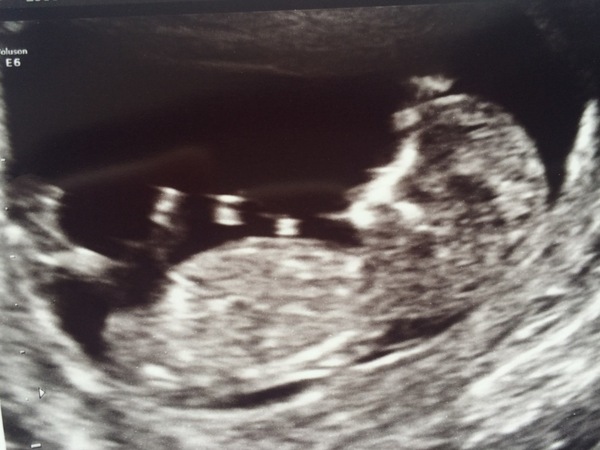

Scan today, it was amazing to see the little thing jumping and waving his/her arms (I had a look at the 'nub' (not visible in this pic) and if you believe in such things it looks like another boy, but obvs can't tell really). NF was 1.3mm so that's a bit reassuring now waiting for blood results.

I've been put back two days so EDD now 16th Dec. GrinGrin